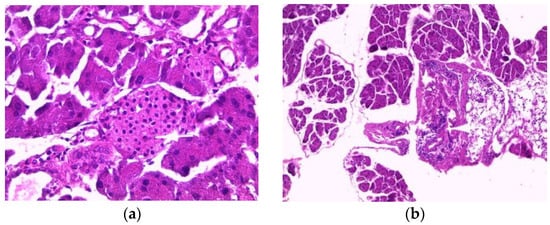

The histology of liver sections from the control mice showed normal hepatocellular architecture as well as well-preserved liver cells, visible central veins and no histological abnormalities (Figure 2a). The liver sections from the aqueous extract (200 mg/kg)-treated groups showed some histological changes, such as intralobular inflammation around the centrilobular veins (CLVs) and cytoplasmic hydropic degeneration of hepatocytes (Figure 2b). In contrast, subacute administration of ethanolic extract caused minimal intralobular inflammation and hydropic degeneration of the cytoplasm, showing binucleated cells and a somewhat enlarged nucleus with blackish pigments (Figure 2c). The liver sections of mice treated with methanolic extract showed an intralobular mononuclear inflammatory focus around the centrilobular veins, hepatocytes with hyperchromatic nuclei, moderate binucleation, vacuolated and enlarged nucleoli, predominant nucleoli (one or two), multinucleated hepatocytes, blackish pigments, and intra sinusoidal (Figure 2d).

Figure 2.

Histopathology of the liver. Histological sections were visualized by hematoxylin and eosin (H and E) staining and observed under a light microscope (OPTIKA Microscopes, Italy) at 40× magnification. (a) Control mice, (b) mice treated with aqueous extract of E. guttatum (200 mg/kg), (c) mice treated with ethanolic extract of E. guttatum and (d) mice treated with methanolic extract of E. guttatum.

Histopathological studies serve as supportive evidence for hematological and biochemical analyses [31]. The photomicrographs of sections of the liver, kidney and pancreas of mice treated orally with extracts of E. guttatum at a dose of 200 mg/kg for 28 days showed histological changes such as an intralobular mononuclear inflammatory focus, a mononuclear inflammatory focus around the centrilobular veins (CLV), hydropic cytoplasmic degeneration of hepatocytes, binucleate cells and a nucleus, a low-bulk, dark-pigment glomerular lesion, interstitial inflammation, plasma cells in the interstitium, and intrapancreatic inflammation. Therefore, these histopathological findings corroborate the biochemical results, and a chronic study is necessary for a complete understanding of the hepatoxicity of this plant.